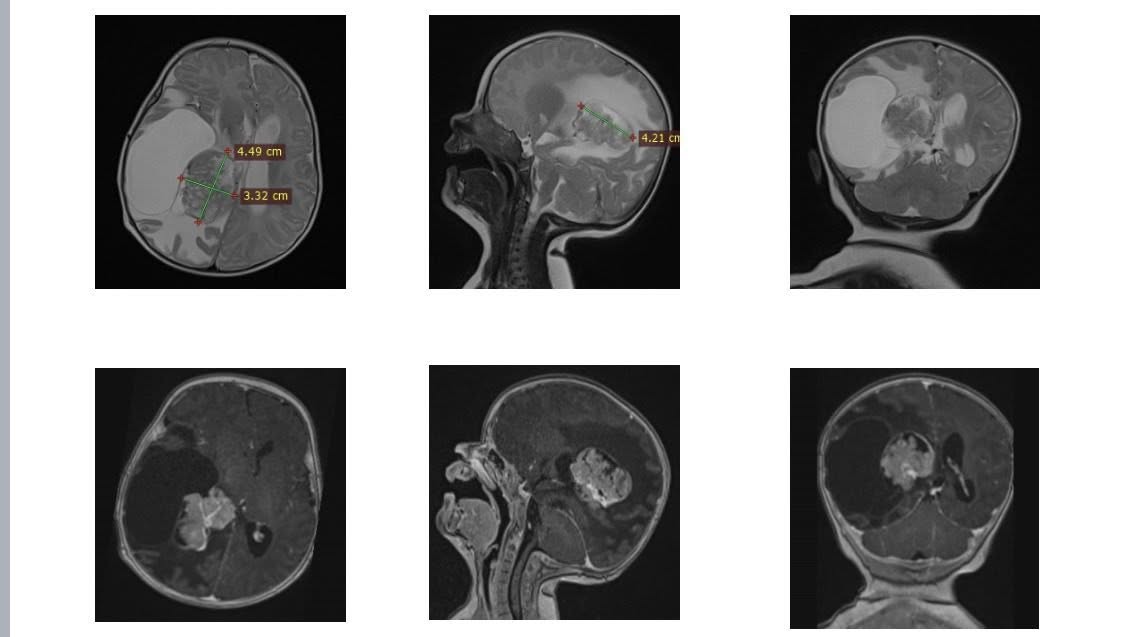

У Львові команда Центру дитячої медицини успішно провела складну операцію маленькій Олівії з Рівного. Дівчинці було всього два місяці, а у правому боковому шлуночку мозку виявили небезпечну пухлину, яка загрожувала її життю. Про це 31 грудня повідомили у пресслужбі медзакладу.

За словами керівника Клініки дитячої нейрохірургії Михайла Ловги, видалення пухлини у такої маленької пацієнтки було дуже ризикованим. Утворення знаходилося біля судинного сплетення та зони, відповідальної за рухи, тож лікарям доводилося працювати максимально обережно.

“На той момент Олівія важила близько 6 кг. Утворення розташовувалося в зоні судинного сплетення з високим кровопостачанням, а отже, з високим ризиком значної крововтрати. До того ж пухлина була близько до ділянки, відповідальної за рухи», — розповів Михайло Ловга.

Саме втручання тривало довше звичайного: лікарі поетапно контролювали крововтрату та обережно видаляли пухлину, щоб не пошкодити рухові зони мозку. Завдяки висококваліфікованій роботі нейрохірургів, анестезіологів, нейрофізіологів та операційних медсестер операція пройшла успішно.